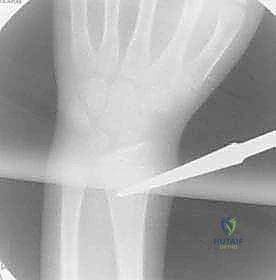

For the radius, the entry point is established distally. A similar 1-2 cm incision is made over the lateral aspect of the distal radius, proximal to the distal radial physis. Extreme caution must be exercised here to identify and protect the superficial branch of the radial nerve (SRN), which courses directly through this operative field.

The awl is introduced just proximal to the physis, again starting perpendicular and angling proximally.

The ulnar nerve runs medially, protected by the flexor carpi ulnaris. Its motor function is critically tested by assessing the adduction of the thumb and the flexion of the ring and small fingers via the FDP. The autonomous sensory zone is the palmar tip of the small finger. Crucially, the ulnar nerve is the most frequent victim of iatrogenic injury during internal fixation, particularly during proximal ulnar approaches or when establishing the entry point for the ulnar intramedullary nail. The radial nerve divides into the posterior interosseous nerve (PIN) and the superficial radial nerve (SRN). The PIN is highly vulnerable during proximal radial exposures, while the SRN, providing sensation to the dorsal web space, is at extreme risk during the establishment of the distal radial entry point for ESIN.

In addition to nail sizing, the surgeon must estimate the degree of rotational malalignment from the radiographs by assessing the cortical widths and the profile of the bicipital tuberosity relative to the radial styloid. The soft tissue envelope must also be factored into the implant selection; in cases of severe swelling, the approach and entry points may need to be slightly modified to avoid excessive tension on the skin edges during closure.